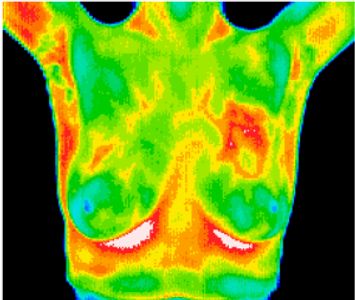

With breast thermography a sensitive camera is used to pick up heat when directed at the breast cancer cells hold onto heat. Skip to content 704 364-2320. BRAS Thermography is dedicated to helping women take control of their own basic preventive.

Breast thermography measures only the breast and results appear in a visual picture whereas computer regulation thermography can detect disorders or irregularities throughout the body. Redding Thermography Arukah Wellness for Women Ashley Houchin CTT 2051 Hilltop Dr. Ad Call Bergen New Bridge Medical Center today to schedule your mammogram.

Ad Top Cancer Center at Crystal Run Health Care. Thermography is a noninvasive test that uses a camera to take images of your. Breast Thermography also known as Breast Thermal Imaging uses a very sensitive digital infrared camera to measure heat on the surface of the breasts.

Thermography can aid in the assessment of various dysfunctions diseases and other concerns in the upper body to include. Thermography R produces an infrared image that shows the patterns of heat on or near the. BTI Thermography locations are found throughout the USA and parts of the world.